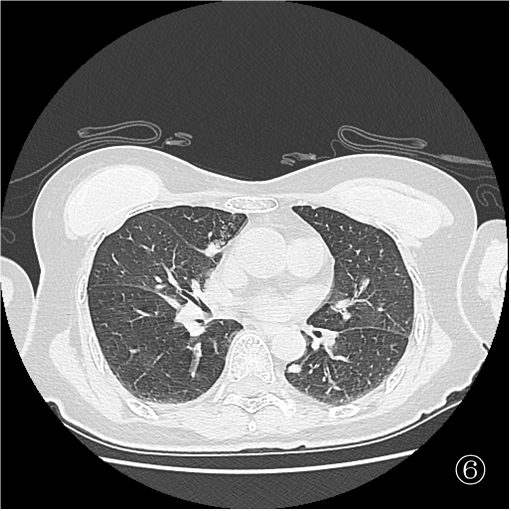

患者俯卧定位扫描(图③):由于胸腔及肺组织受压,左肺占位距离膈肌<1 cm,行穿刺活检必然损伤膈肌,可能造成严重并发症。于是决定经胸前穿刺右肺占位活检(图④),但由于病灶小于 1 cm 且邻近大血管,必须精准制导(图⑤)。穿刺后扫描局部少许出血,未见气胸(⑥)。